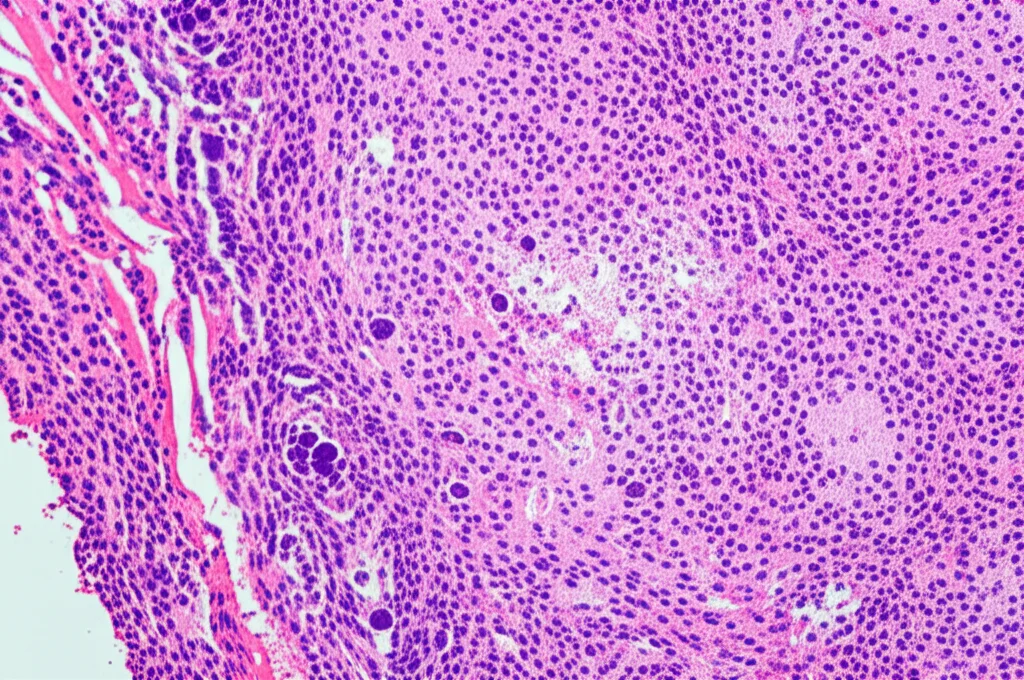

- Tipo di cancro: i più comuni erano l’adenocarcinoma (38.8%) e il carcinoma a cellule squamose (36.3%).